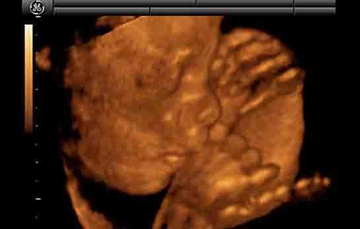

23 haftalık gebelik, hamileliğin ikinci trimesterinin sonlarına yaklaşıldığı bir dönemi ifade eder. Bu süre zarfında, hem anne hem de bebek için birçok önemli gelişim ve değişiklik yaşanmaktadır. Bu makalede, 23 haftalık gebelik dönemindeki fiziksel ve duygusal değişimlerin yanı sıra, bebeğin gelişimi, anne adayının sağlığı ve dikkat edilmesi gereken hususlar ele alınacaktır. Bebeğin Gelişimi23 haftalık gebelikte bebek, hızla büyümeye devam etmekte ve birçok önemli gelişim sürecinden geçmektedir. Bu dönemde, bebeğin gelişimiyle ilgili bazı önemli noktalar şunlardır: